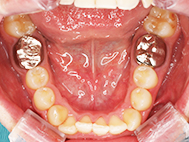

After

| 症状 | 上顎前歯部叢生 |

上の前歯がハの字隣の歯が引っ込んでいる

前歯のガタガタが気になるとの事で来院されました。

装着が目立ちたくないとの事でアライナ-での矯正を希望されました、歯の間を削り少し歯の幅をスリムにして綺麗なアーチに並びました。